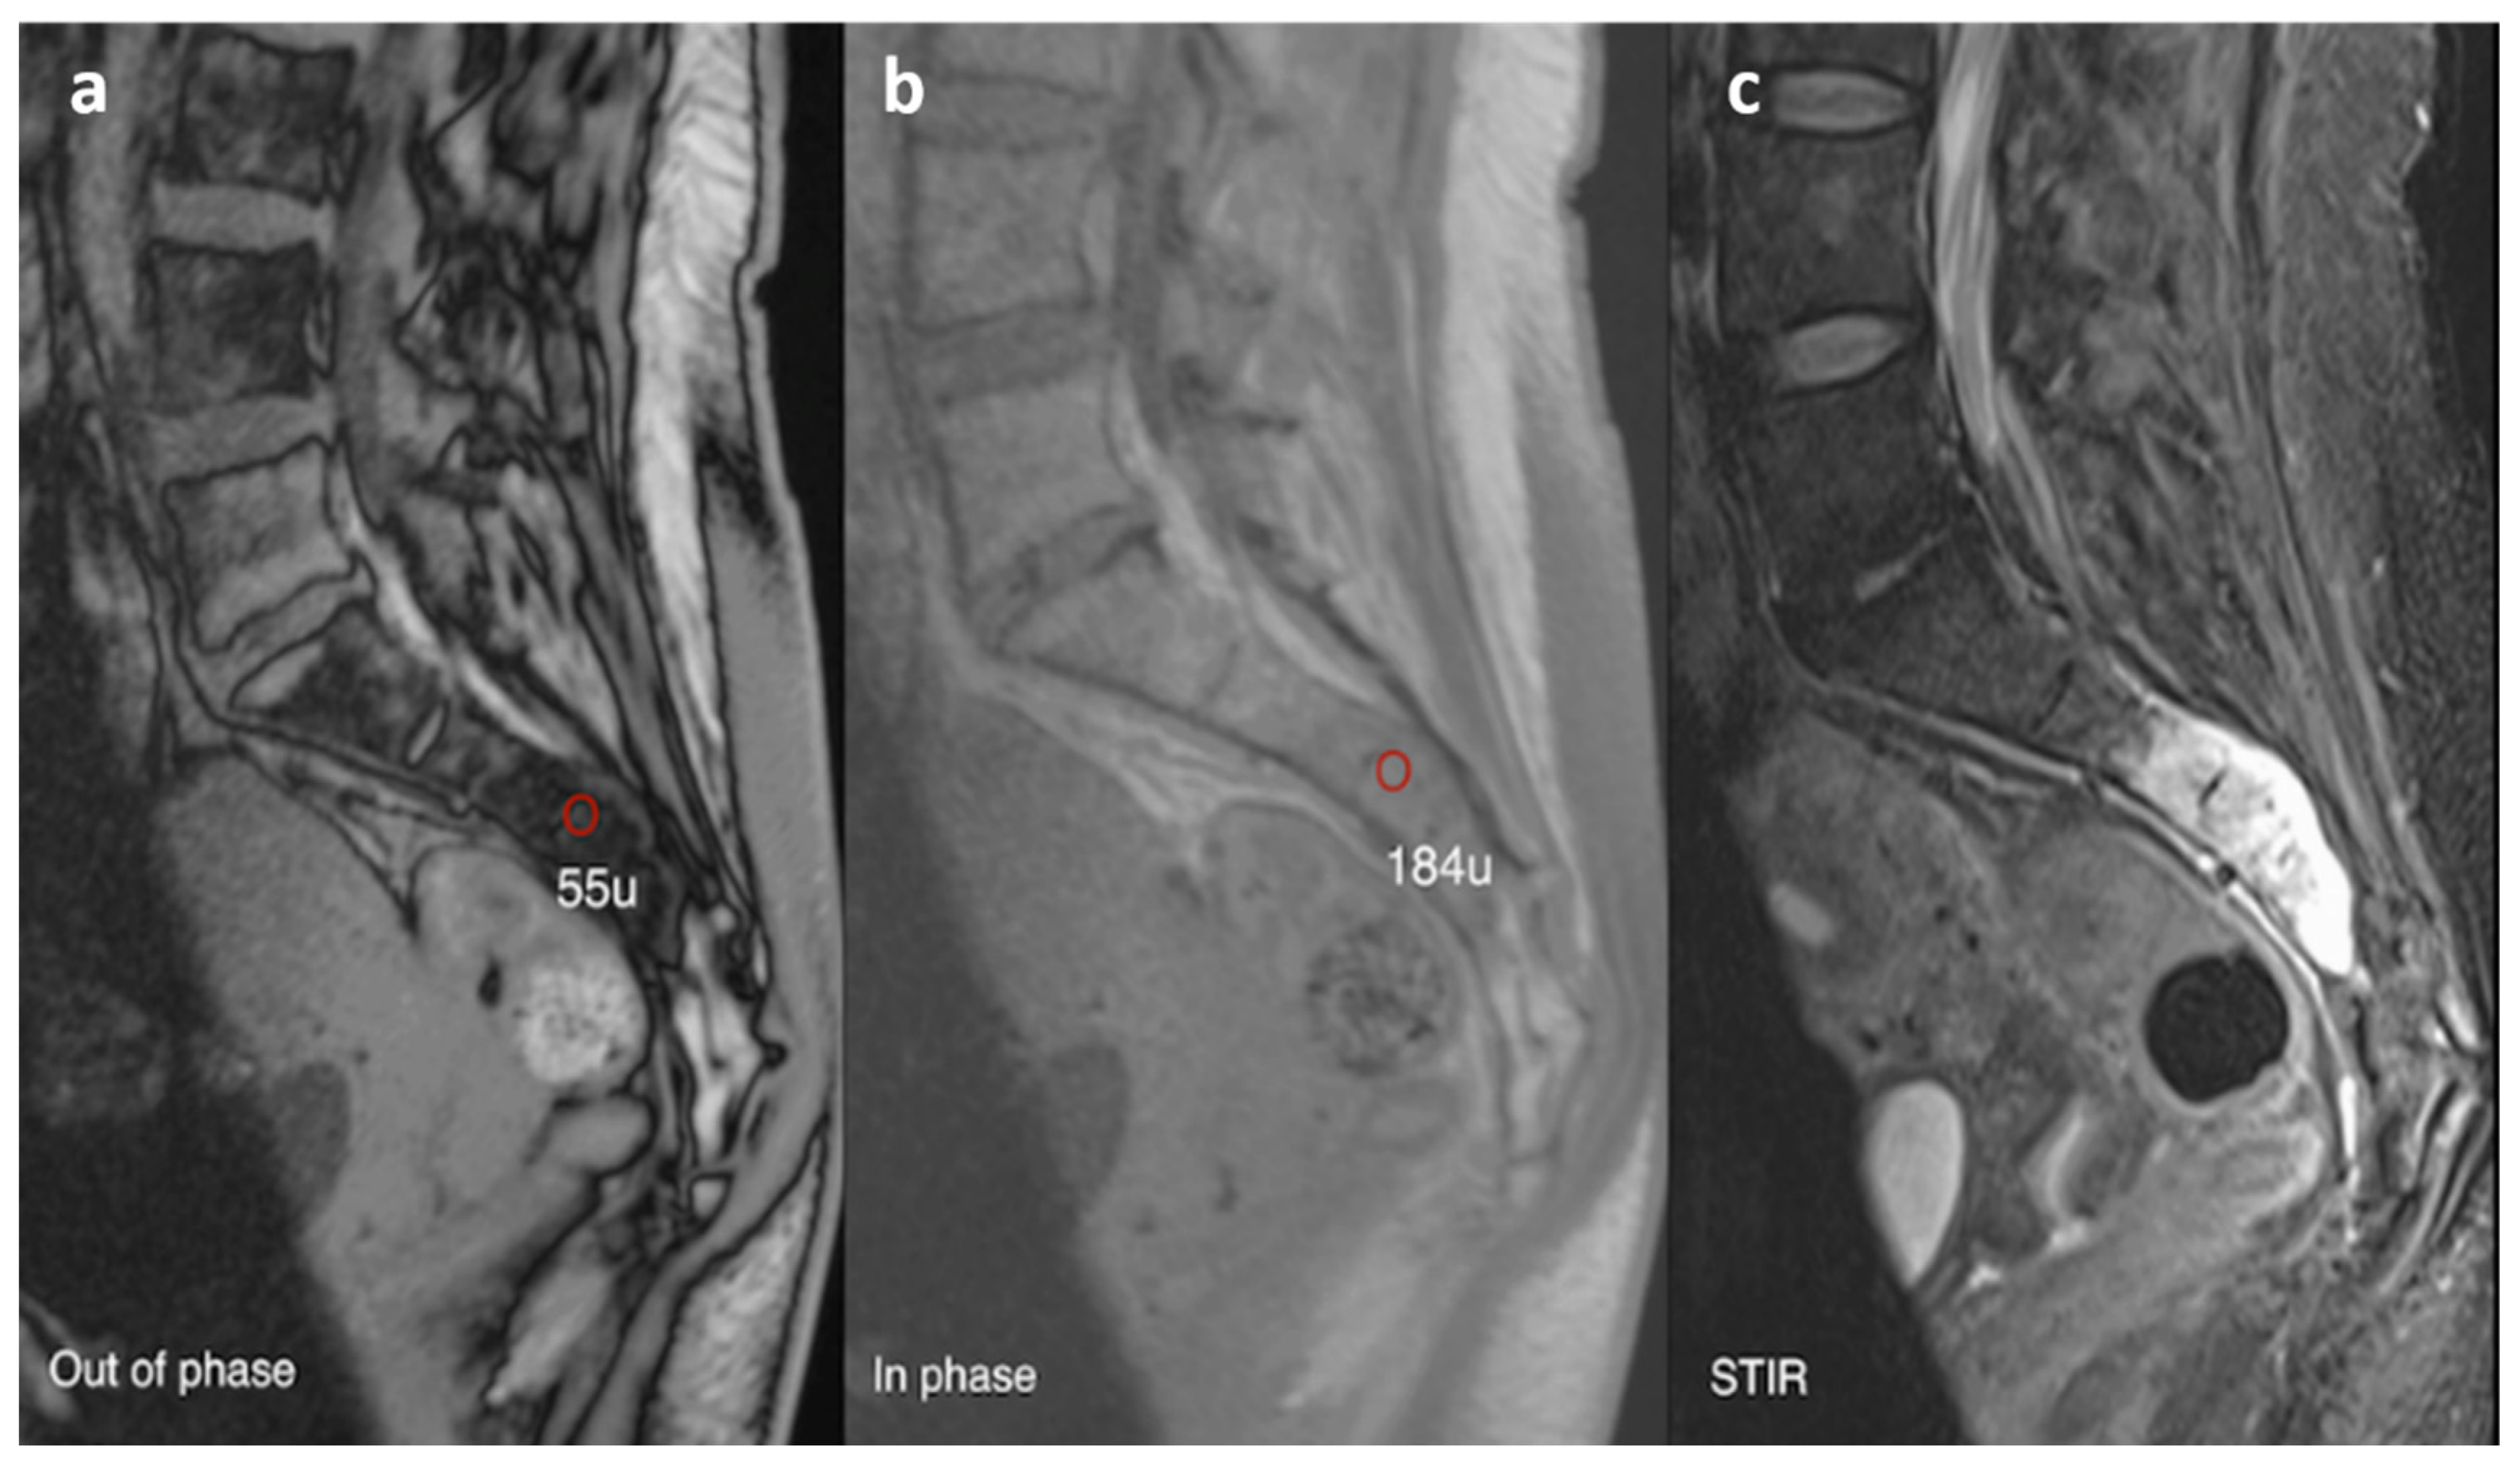

| Haemangioma | Honey comb appearance. ‘Corduroy’ and ‘polka dot’ signs. | Usually T1 and T2 hyperintense due to fat content. Signal drop out >20% on out of phase chemical shift imaging. |